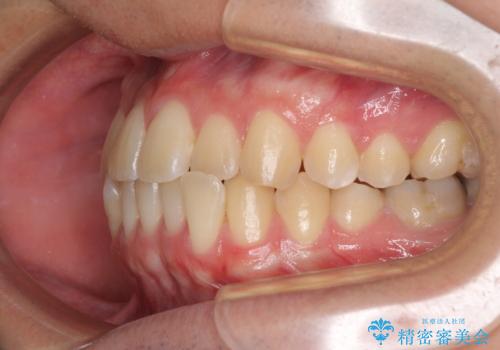

【モニター】前歯のクロスバイトと隙間を改善 インビザラインによる矯正治療

- 前歯のクロスバイトを気にして来院された患者様です。

骨格的には問題がなかったため、インビザラインを用いて咬み合わせを改善していくこととしました。

インビザライン特有の、奥歯の咬み合わせの問題もなく、しっかりと歯列を改善することができました。

舌側転位している上顎側切歯(内側に引っ込んでいる真ん中から2番目の歯)は、インビザラインが最も移動を苦手とする歯であり、これ以上の改善を望まれる場合にはワイヤー矯正、あるいはワイヤー矯正の併用をお勧めいたします。